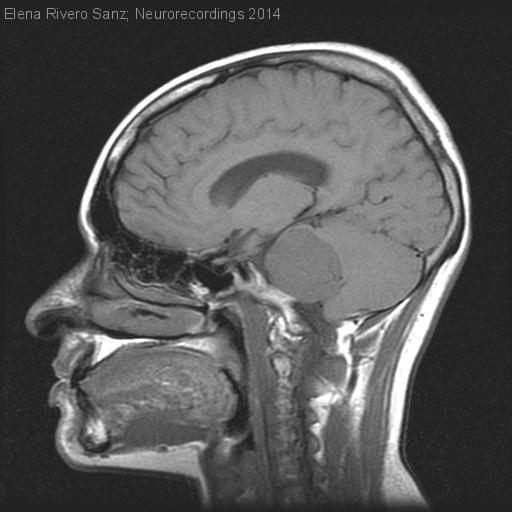

Neurinoma acústico de gran tamaño

Mujer | 28 años

Diagnóstico final: Neurinoma del VIII par de gran tamano

Neurología: Neurooncología | Neurootología

Etiología: Neoplasias